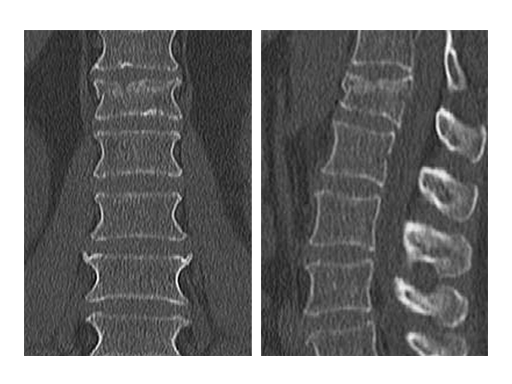

X-rays and CT scans were performed for preoperative analysis, definition of the fracture type and surgical pre-op planning.

The lateral x-ray and CT scans showed a typical wedge deformity of the fractured vertebral body (L1). The fracture included the cranial endplate as well as the anterior and posterior wall.

Additionally, a MRI scan was performed to analyze the integrity of the soft tissue in detail. The lateral MRI clearly showed a ruptured intervertebral disc at the level T12/L1.

Based on the Magerl Classification [1], the final classification of the fracture concluded in AO Type A 3.1.1. This fracture type is also referred to as an instable incomplete burst fracture including posterior wall involvement.